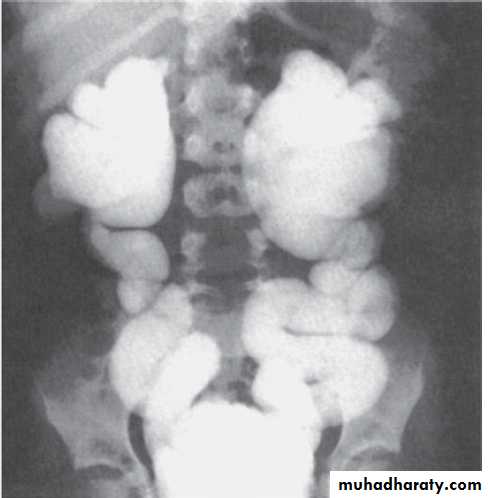

KUB

Multiple bilateral renal stonesStaghorn stone needs PCNL